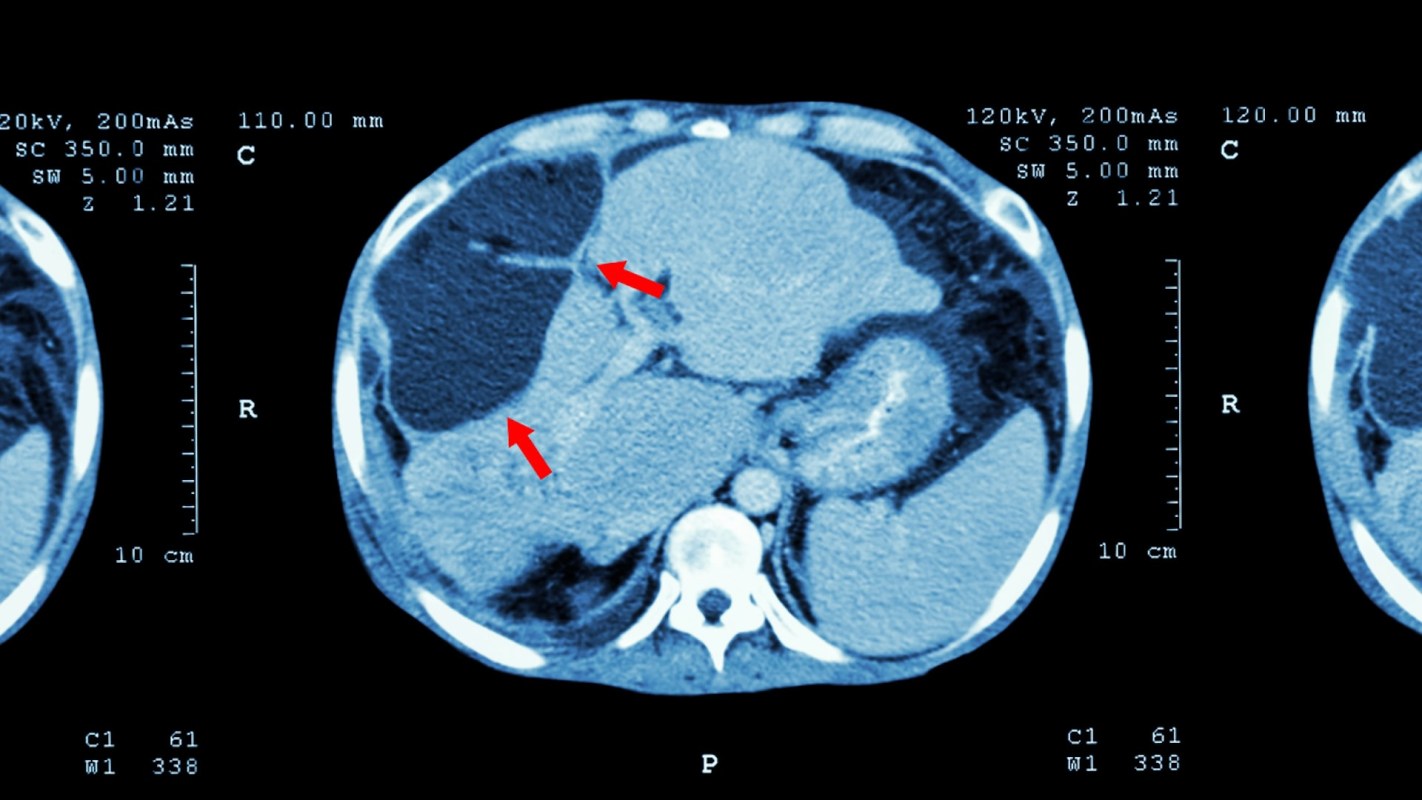

A new study in Nature journal Scientific Reports has uncovered a link between polystyrene microplastics and the development of liver fibrosis. The study conducted on mice investigated how long-term exposure to microplastics could drive the development of liver fibrosis and increase liver inflammation, as well as liver lipid deposition. Excessive lipid accumulation puts the liver at risk of diseases like cirrhosis and steatosis (fatty liver disease).

Per the study from Wuhan University researchers in China, long-term exposure to microplastics significantly affects the liver, with inflammation and abnormal lipid deposition being identified as the main contributors to the development of liver fibrosis, confirming that chronic exposure to microplastics, even in low concentrations, can cause liver fibrosis.